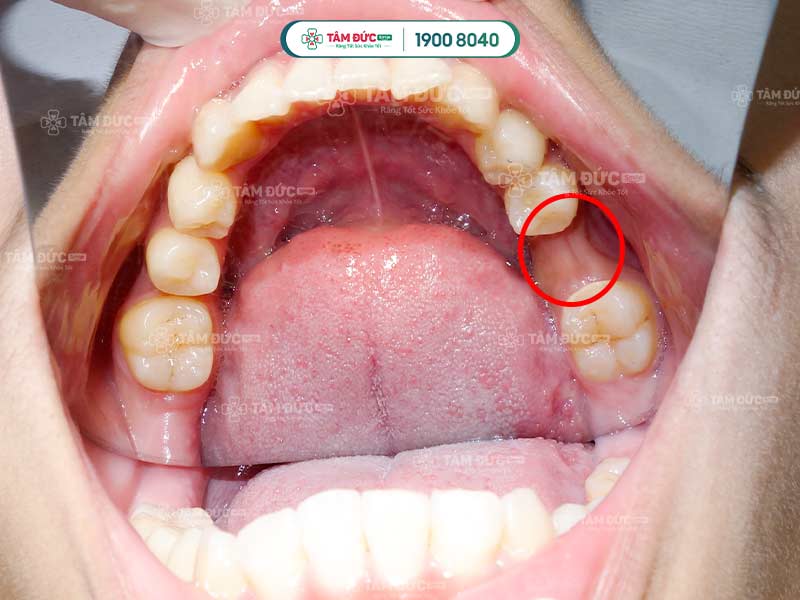

Thống kê cho thấy, tình trạng này thường xuất hiện ở các răng phía ngoài như răng nanh, răng cửa.

2.5. Tiêu xương ổ răng làm tụt lợi hở chân răng

Khi xương ổ răng bị mất dần do các yếu tố như di truyền, suy dinh dưỡng, thì phần chân răng sẽ bị lộ ra ngoài. Lớp nướu không còn được nâng đỡ dần trở nên lỏng lẻo và bị kéo tụt xuống.

Tiêu xương ổ răng càng nghiêm trọng càng đẩy nhanh tiến độ bị tụt lợi hở chân răng. Việc bổ sung đầy đủ dinh dưỡng và phòng ngừa tiêu xương răng là rất cần thiết để ngăn ngừa tụt lợi.